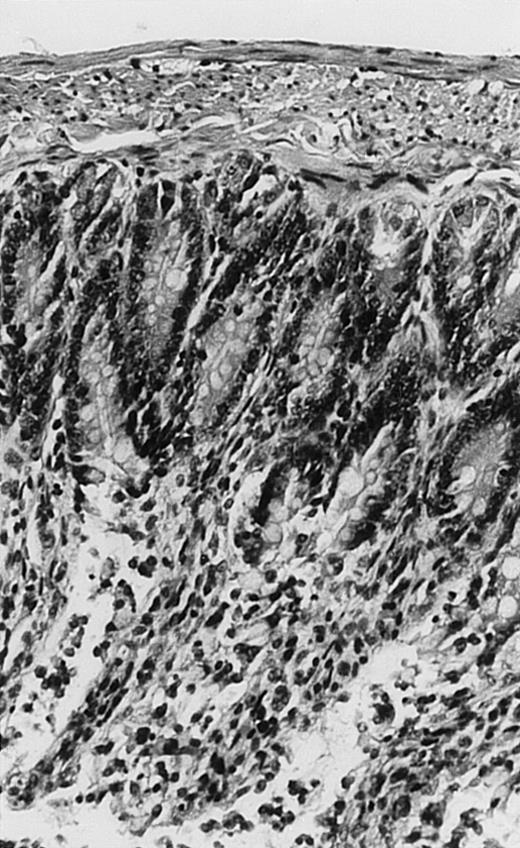

Pathologic findings in the small and large intestine were strikingly different depending on the treatment group. Figure 2A shows a representative pathologic sample from an animal assigned to the control group. Marked thinning of the bowel wall and extensive areas of epithelial cell sloughing was noted. Animals randomized to rhG-CSF treatment had minimal improvement in histologic findings with focal regions of preserved epithelium (Fig2B). Animals randomized to the rhIL-11 group showed substantial improvement with thickening of the epithelial layer and preservation of mucosal cell integrity (Fig 2C). Animals receiving both rhG-CSF and rhIL-11 had the most favorable histologic findings with normal mucosal thickness, minimal inflammatory changes, and preserved tissue architecture (Fig 2D). The composite analysis of the gastrointestinal pathology is provided in Table 1.

Histopathology of small intestinal mucosa cut in transection from an animal in each treatment group (study day 8). The upper panel (row 1) is a low power view (original magnification × 57); the lower panel (row 2) is a high power view (original magnification × 144). Note the diffuse thinning and necrosis of the mucosa with sloughing of intestinal epithelial cells in the control animal (A). There is progressive recovery of the thickness of the mucosa, reduction in inflammatory changes, and improved epithelial architecture with rhG-CSF (B), rhIL-11 (C), and combination therapy with rhG-CSF+IL-11 (D).

rhIL-11 has been shown to have marked effects on gastrointestinal epithelial surfaces. rhIL-11 blocks apoptosis of epithelial cells exposed to radiation and chemotherapy in mice.22 rhIL-11 is protective in a variety of mucositis models and in models of intestinal inflammation.4,23,24 rhIL-11 has been shown to prolong the G-0 phase of growth of intestinal epithelial cells. The precise mechanism of action is not known, but it has been observed that rhIL-11 decreased pRB (retinoblastoma protein) phosphorylation (an important signaling event in cell cycling) within intestinal epithelial cells.32 rhIL-11 has protective effects on gastrointestinal mucosa in transgenic rats, which possess HLA-B27 antigens.4These animals develop an inflammatory colitis that is similar in many respects to human inflammatory bowel disease. rhIL-11 treatment in these animals decreases intestinal inflammation and chronic diarrhea. Based on these preclinical findings, rhIL-11 is currently in clinical trials in both inflammatory bowel disease and chemotherapy-induced mucositis.33 The remarkable capacity of rhIL-11 to protect the gastrointestinal mucosal integrity after chemotherapy is apparent in the current series of experiments (Fig 2).

The beneficial effects of rhIL-11 in the neutropenic rat model may be mediated by its activity as a hematopoietic growth factor, an antiinflammatory cytokine, or its ability to maintain gastrointestinal epithelial integrity.25,33 The results of the current study would favor rhIL-11 protective effects on the intestinal epithelium as the principal mechanism protection in these animals. Maintenance of the gastrointestinal barrier function should diminish the frequency of gut translocation-derived bacterial infection after chemotherapy-induced myelosuppression and epithelial injury.25 The remarkable preservation of membrane integrity found on the gastrointestinal pathologic samples, the reduced circulating levels of endotoxin, and the reduced bacterial load in organ cultures support a dominant role for epithelial protective effects by rhIL-11 treatment in this animal model.